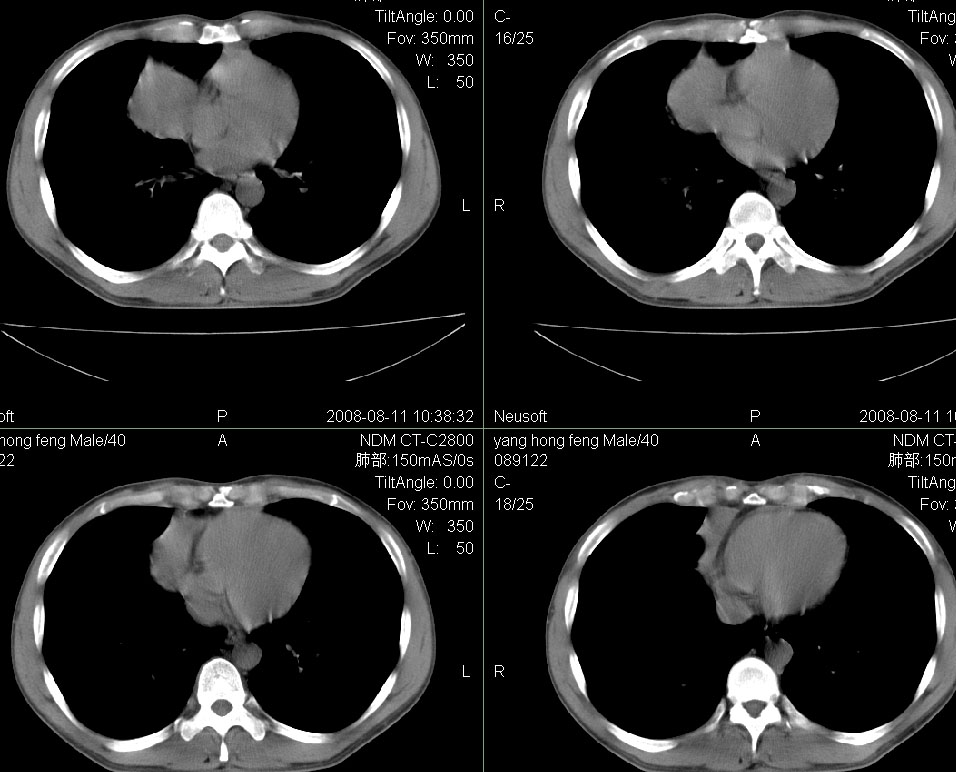

标题: CT15138:男,40,咳嗽胸痛. [打印本页]

标题: CT15138:男,40,咳嗽胸痛.

外院穿刺未见癌细泡,结核菌素实验阳性,未正规治疗2个月复查病灶及纵隔淋巴结增大

结合病史及临床表现考虑右侧中心型肺癌纵隔转移,

右侧中心型肺癌纵隔转移!

右肺中叶肺癌,纵隔淋巴结转移.

右侧中心型肺癌纵隔转移

考虑右肺中叶周围型肺癌并纵隔淋巴结转移。